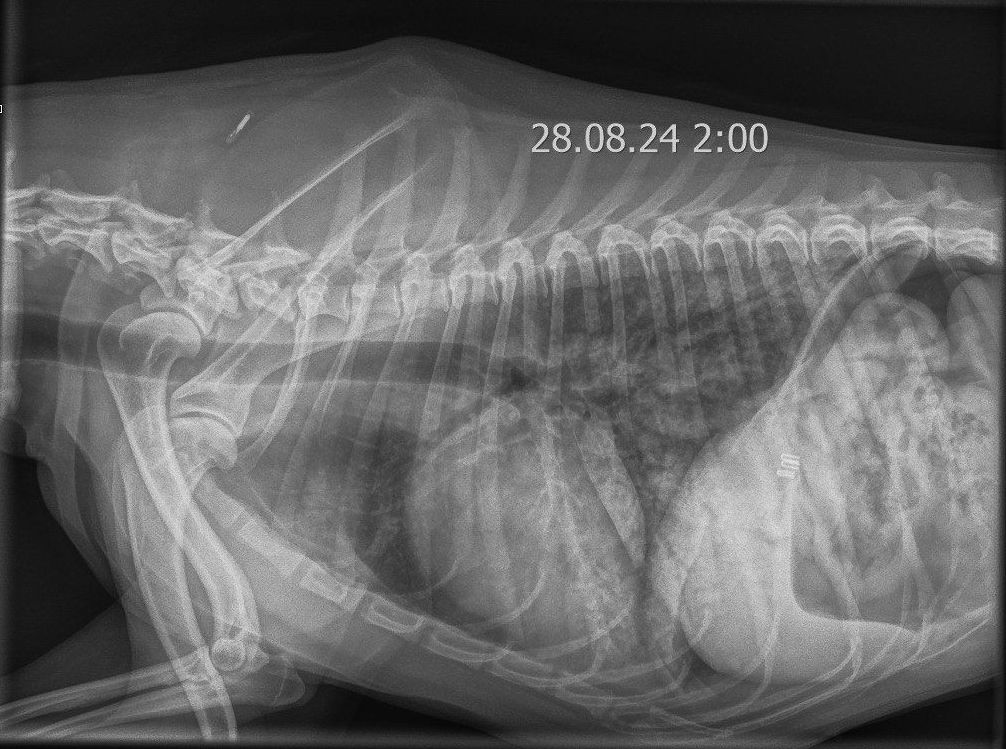

На пятые сутки, спустя двое суток после операции, общее состояние пациента и результаты анализов крови улучшились, активность увеличилась, собака стала более эмоциональной, но самостоятельный аппетит по-прежнему отсутствовал. Диарея не наблюдалась, жажда и мочеиспускание оставались без особенностей. Болезненность брюшной стенки оценивалась как легкая. Были отменены мультимодальная анальгезия, поддерживающая инфузионная терапия и смекта. Однако появились новые симптомы: кашель и увеличение частоты дыхательных движений во сне до 30 дых. дв./мин, без признаков диспноэ. Уровень насыщения крови кислородом (SpO2) без дополнительной оксигенотерапии составлял 93–95%. При рентгенологическом исследовании были выявлены преимущественно диффузные альвеолярные затемнения легочной ткани, охватывающие почти все поля легких. Наибольшая площадь поражения наблюдалась в каудальных долях обоих легких (рис. 9). Данные изменения в совокупности с установленным диагнозом указывали на высокую вероятность геморрагий в легочной паренхиме как одного из проявлений лептоспироза.

Синдром лептоспирозного легочного кровотечения (англ. leptospiral pulmonary haemorrhage syndrome; LPHS) является тяжелым проявлением острого лептоспироза и в последние годы все чаще диагностируется у собак и других видов животных14. Гистопатологические поражения легочной ткани при LPHS имеют схожие характеристики у разных видов и проявляются различной степенью внутриальвеолярного кровоизлияния при отсутствии выраженного воспалительного клеточного инфильтрата или васкулита. Внутриальвеолярный отек, фибрин и гиалиновые мембраны, характерные для патологий с диффузным альвеолярным повреждением (например, острый респираторный дистресс-синдром; ОРДС), также могут наблюдаться при LPHS, но не являются доминирующими признаками15. Патогенетические механизмы LPHS плохо изучены. В настоящее время исследуются несколько гипотез, включая системные воспалительные, иммуноопосредованные и прямые эффекты, вызываемые лептоспирами. Внутриальвеолярное кровоизлияние может быть обнаружено даже у собак без явных респираторных признаков17. Это указывает на то, что LPHS может быть более распространенным у собак с лептоспирозом, чем принято считать. Рентгенографические изменения, указывающие на LPHS, обычно первоначально проявляются в каудодорсальных отделах легочных полей и, как правило, носят двусторонний и недолевой характер. Поражения варьируются от легкого интерстициального рисунка до легкого или тяжелого ретикулонодулярного легочного рисунка с очаговыми альвеолярными инфильтратами. У некоторых собак наблюдается небольшое количество плеврального выпота (рис. 10). Рентгенографические изменения могут присутствовать даже при отсутствии клинических признаков респираторных нарушений26.